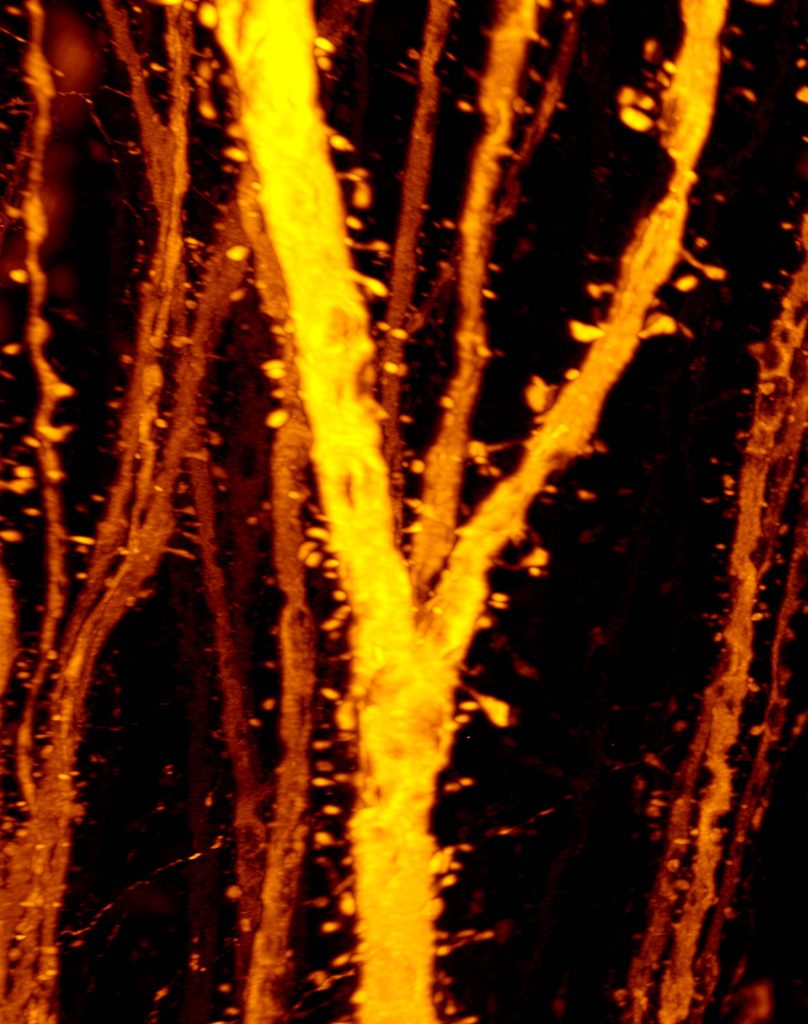

Egashira-san and Ke-san’s new paper was published in Science Advances! We found that dendritic compartment-specific spine formation is critical for the cortical maturation during adolescence. We alsofound that adolescent spine formation is impaired in schizophrenia model mice. Congraturations!!!